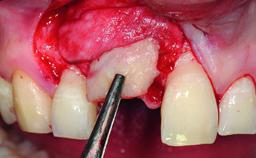

Replacement of an Ankylosed Upper Left Central Incisor: Bone Augmentation and Socket Grafting, Late Placement of an RC Bone Level Implant

A 15-year-old male patient was referred to us by his pediatric dentist in June 2004 for evaluation of treatment options for his failing tooth 21. The patient had recently seen an endodontist for internal bleaching and been advised that there had been significant resorption and ankylosis. The patient’s mother was concerned because the tooth appeared shorter than the adjacent one. His past dental history was significant for trauma (September 2001), where the tooth had been avulsed and reimplanted. Teeth 11 and 21 had been endodontically treated.

Bone Augmentation Horizontal|Simultaneous|Staged

Augmentation Materials Autogenous chips|Xenogenous

Bone Volume Deficient horizontally, requiring prior grafting